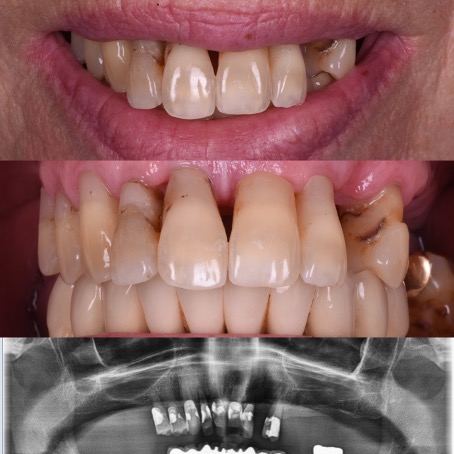

All-on-4®

Édentation totale de la mâchoire – restauration complète fixe avec des implants dentaires

Avant

Après

Selon les techniques modernes de mise en charge immédiate pour les patients édentée, nous avons la possibilité, dans la plupart des cas, d’offrir des dents fixes aux patients dans la journée.

Le protocole All-on-4® permet de réaliser immédiatement une prothèse fixe avec seulement quatre implants par mâchoire. Les implants du fond sont mis en place avec une inclinaison de 30 à 45 degrés, dans les cas où des dents encore présentes devraient être extraites le tout est fait pendant la même opération, la journée se termine pour le patient avec l’installation des dents fixes dans le 90% des cas. Une prothèse définitive sera réalisée environ 4 mois plus tard.